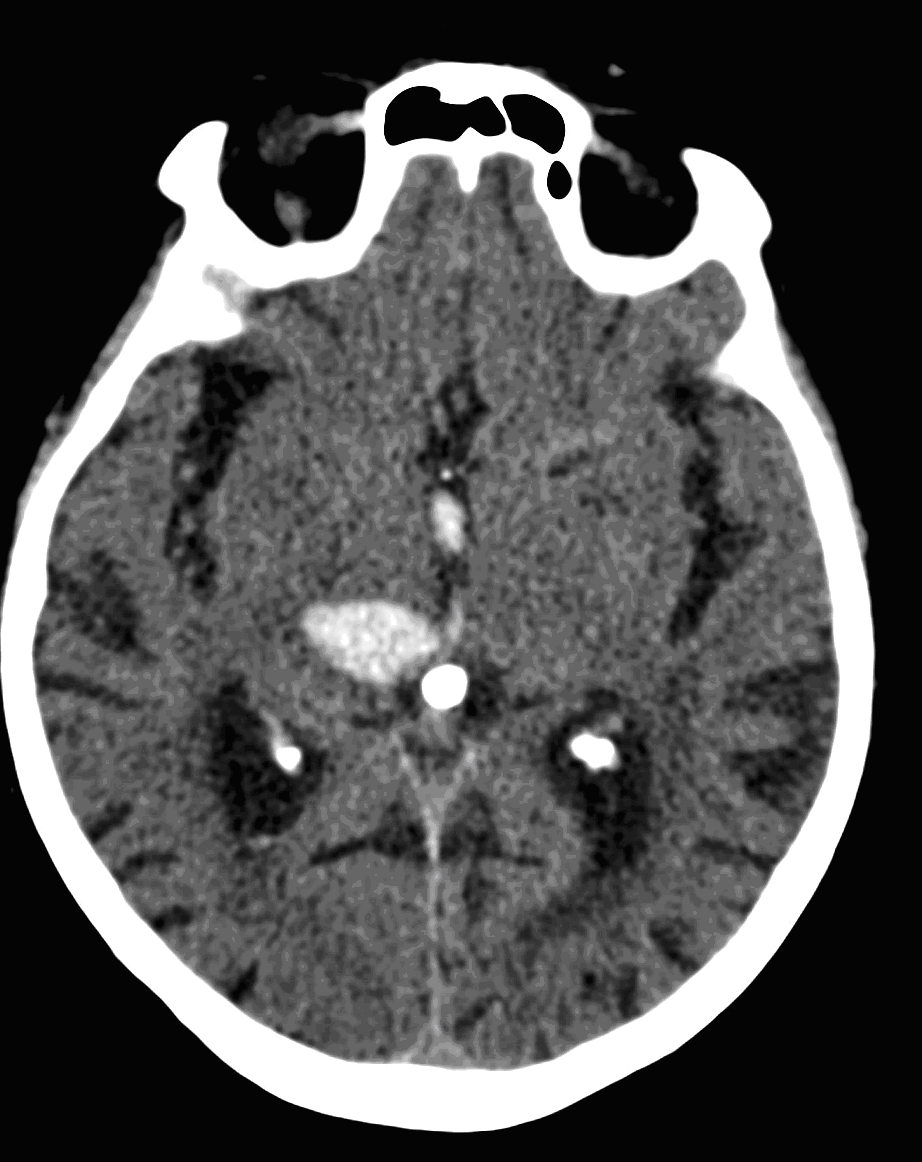

Parenchymal hemorrhage most often occurs in patients with hypertension, after malignant hypertensive states. The initial localization for its occurrence is at the basal ganglia (putaminal-claustral hemorrhage) that can extend into the ventricles or to the subarachnoid space. The mean age of these patients is usually younger than that of the ones with ischemic infarcts.

Bleeding usually originates from saccular “berry” aneurysms (on the branches of the Circle of Willis). Aneurysm rupture besides subarachnoid hemorrhage can also cause intraparenchymal bleeding when it breaks into the parenchyma.

The so called lobar hemorrhage is usually caused by tumor bleeding, hemorrhagic vascular malformations, rebleeding of ischemic infarcts. Bleeding secondary to cerebral amyloid angiopathy frequently occurs in the elderly without prevalent hypertension. It often presents as a sequential hemorrhage, each bleeding following one another, resulting in various ages of hemorrhages.

On CT images acute bleeding always presents as hyperdensity. (One has to keep it mind that hyperdensity of the blood is affected by the hematocrit levels, hence making the diagnosis more difficult.) Intraparenchymal blood is dominated by a destructive appearance (mass-effect) and it is surrounded by hypodensity as a sign of perifocal edema. It often breaks into the ventricles. In patients lying in a supine position they collect (sediment) at the occipital horn of the lateral ventricles, creating a hyperdense liquid-to-liquid levels. Later on, the density of blood decreases and shows a peripheral ring or rim-like contrast enhancement without mass-effect.